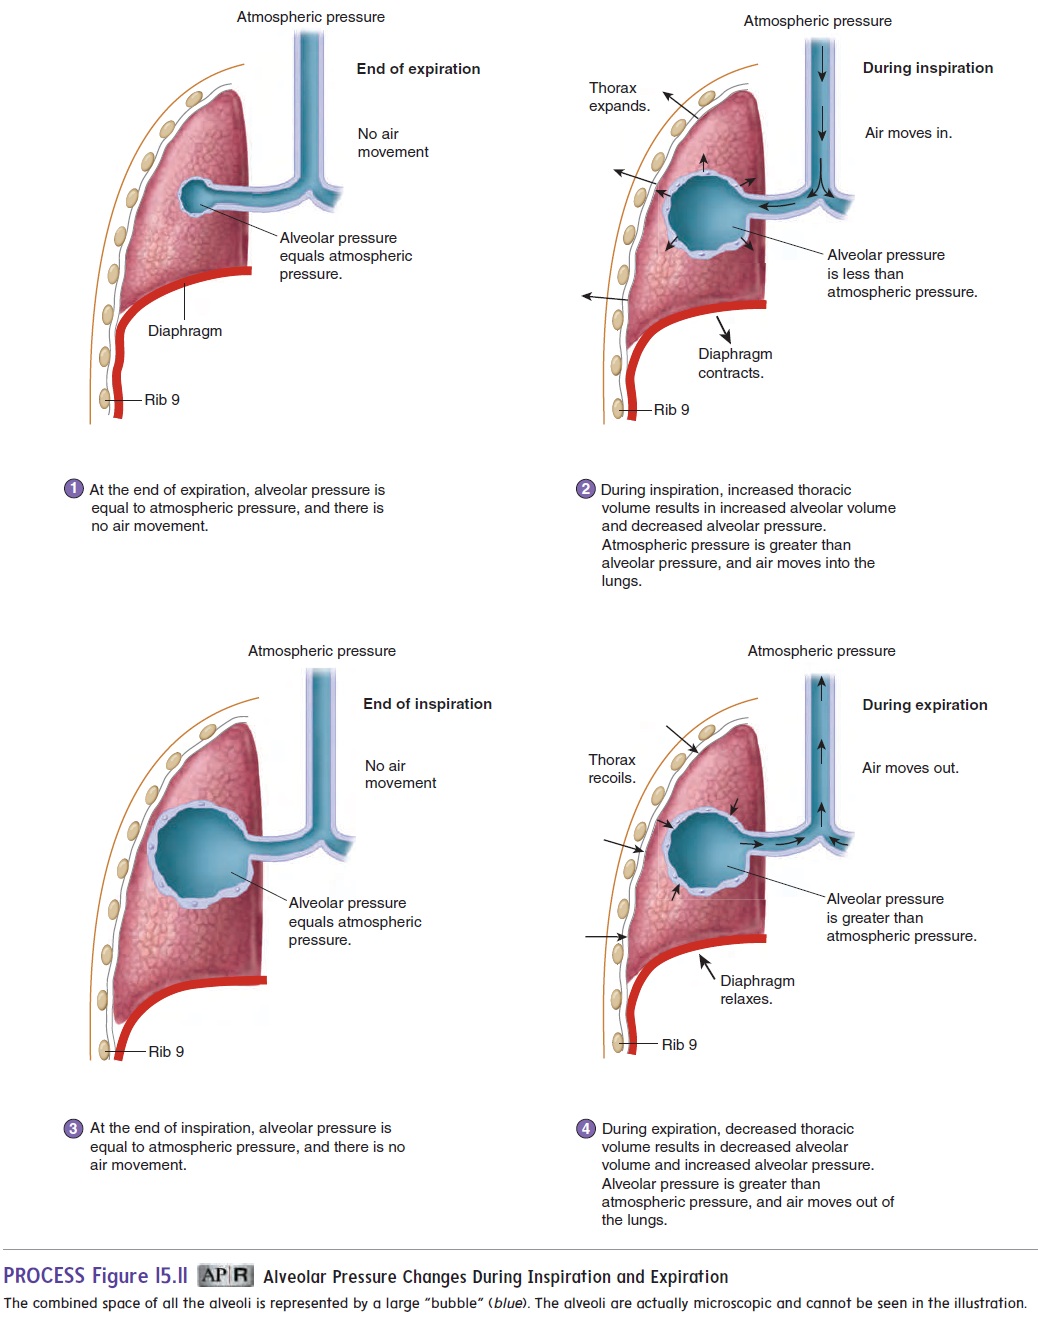

The diaphragm and external intercostals mediate inspiration and expiration by contracting or relaxing During inspiration the external intercostals and the diaphragm contract expanding the chest wall From a physiological standpoint the lung volumes are either dynamic or static Both subclasses are measured at different degrees of inspiration or expiration however dynamic lung volumes

Results The breathing with mainly inspiration group BMIG showed significant differences in chest size during inspiration CSI chest expansion values CEVs forced vital Pulmonary ventilation comprises two major steps inspiration and expiration Inspiration is the process that causes air to enter the lungs and expiration is the process that causes air to leave the lungs Figure 22 3 3 A respiratory cycle

Inspiration And Expiration Chest Size - The diaphragm and external intercostals mediate inspiration and expiration by contracting or relaxing During inspiration the external intercostals and the diaphragm contract expanding the chest wall